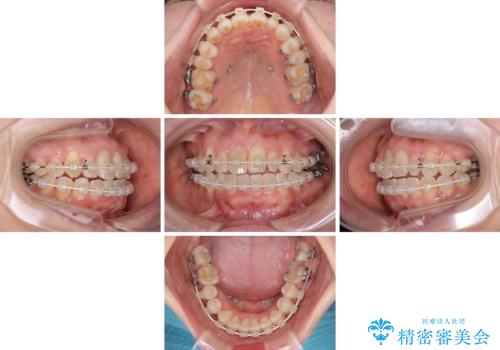

骨格的なズレを歯列矯正でカバー ワイヤー装置での非抜歯矯正

- 前歯のデコボコと咬み合わせの悪さを気にして来院された患者様です。

下顎骨が左側にズレて成長してしまったため、左側の咬み合わせが上下反対になっている状態でした。

骨格的なズレは歯列矯正のみでは改善できず、骨切除が必要となります。

そこまでの処置は望んでいらっしゃらなかったため、歯列矯正でのカムフラージュにより咬み合わせを改善することとしました。

予想通り左側の咬み合わせの調整に苦労をしましたが、最終的には違和感のない咬み合わせを達成することができました。